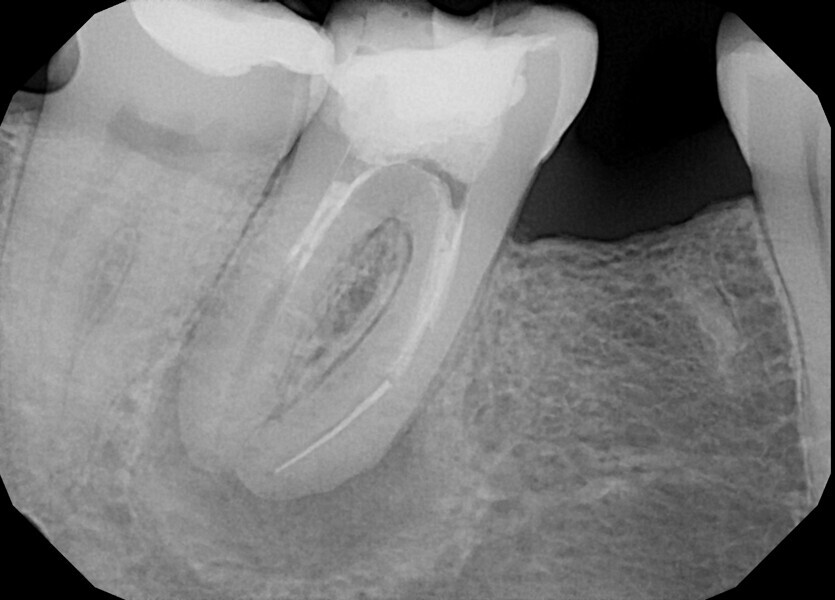

The patient was referred to Dr Witkowski’s dental office for endodontic treatment of teeth #31 and 41 (Fig. 2). After examination, endodontic treatment was performed (Fig. 3). In tooth #41, the access cavity was done by the referring dentist (Fig. 4a). In tooth #31, the access cavity was designed and performed (Fig. 4b). After this step, preparation of the canal space was done, in tooth #41 up to 25/0.04 and in tooth #31 up to 20/0.04 with VDW.ROTATE (VDW; Fig. 5). The next step was the irrigation protocol, which was performed with an Er,Cr:YSGG laser (BIOLASE) at 1.5 W and 100 Hz in both teeth. The canals were prepared for obturation. In tooth #41, obturation was done with a single point and CSBS, and in tooth #31, the piston technique was performed (Fig. 6). A control radiograph was taken immediately after the treatment (Fig. 7). Healing of the lesion was visible on the follow-up radiograph performed six months after the treatment (Fig. 8).

Fig. 7.